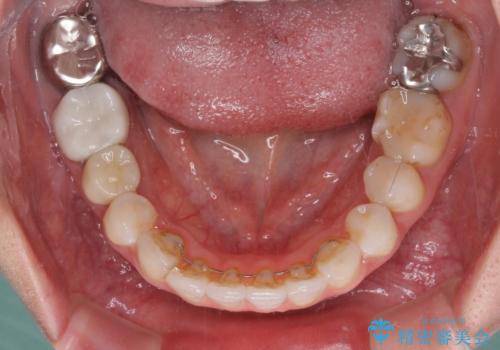

総合歯科治療 矯正治療と失活歯のセラミック補綴治療

- 失活により変色した歯と不揃いな口元を気にして来院された患者様です。

口元をインビザラインにより歯列を整え、その後に失活している奥歯をオールセラミッククラウンにて補綴治療することとしました。

長時間のマウスピース装着と、患者様自身でのゴムかけに協力いただき、自然な口元に仕上げることができました。

気になっていた変色した歯もオールセラミッククラウンで本物の歯のようになり、患者様には大変満足していただきました。